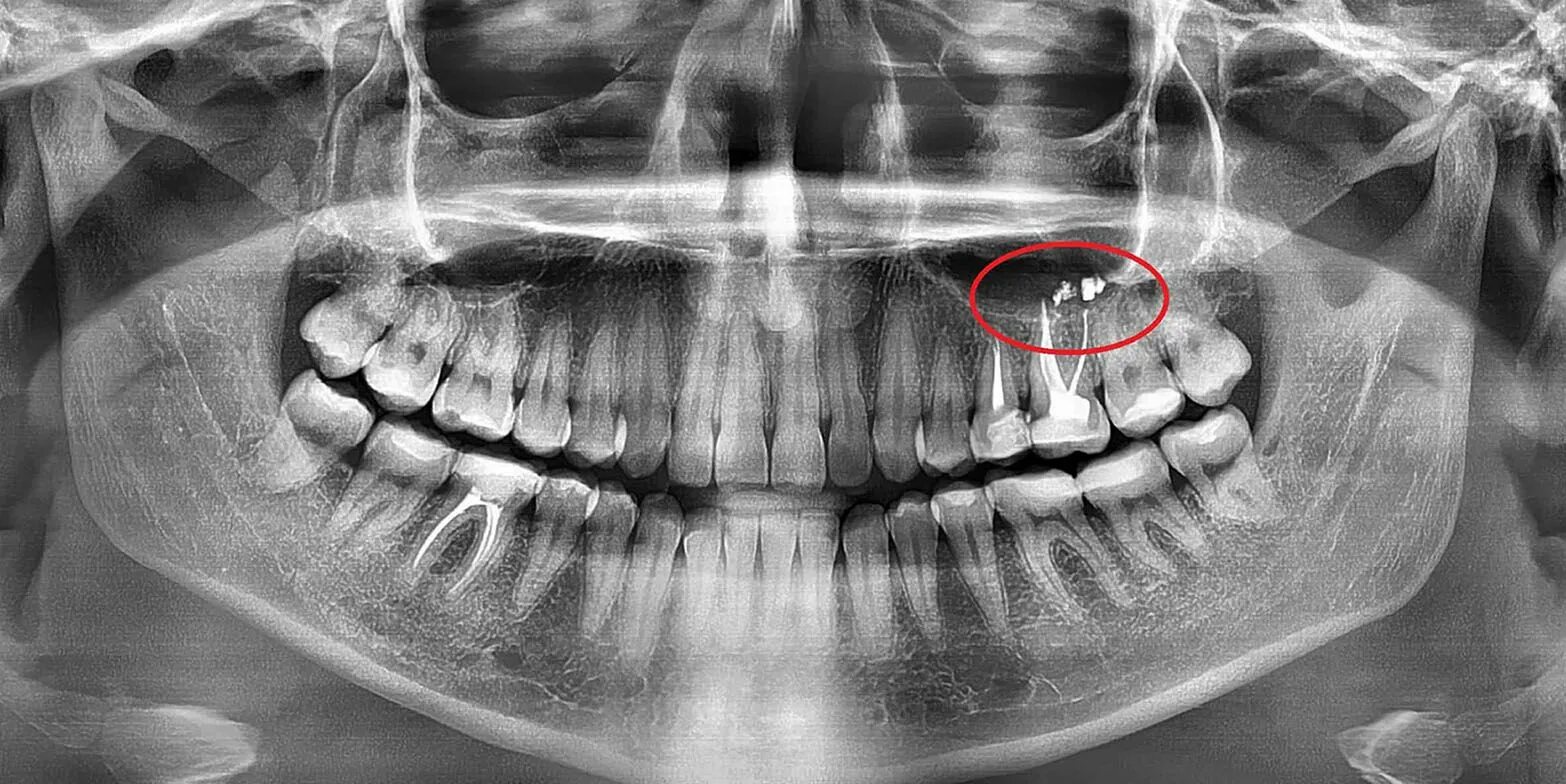

Насморк отдает в зубы